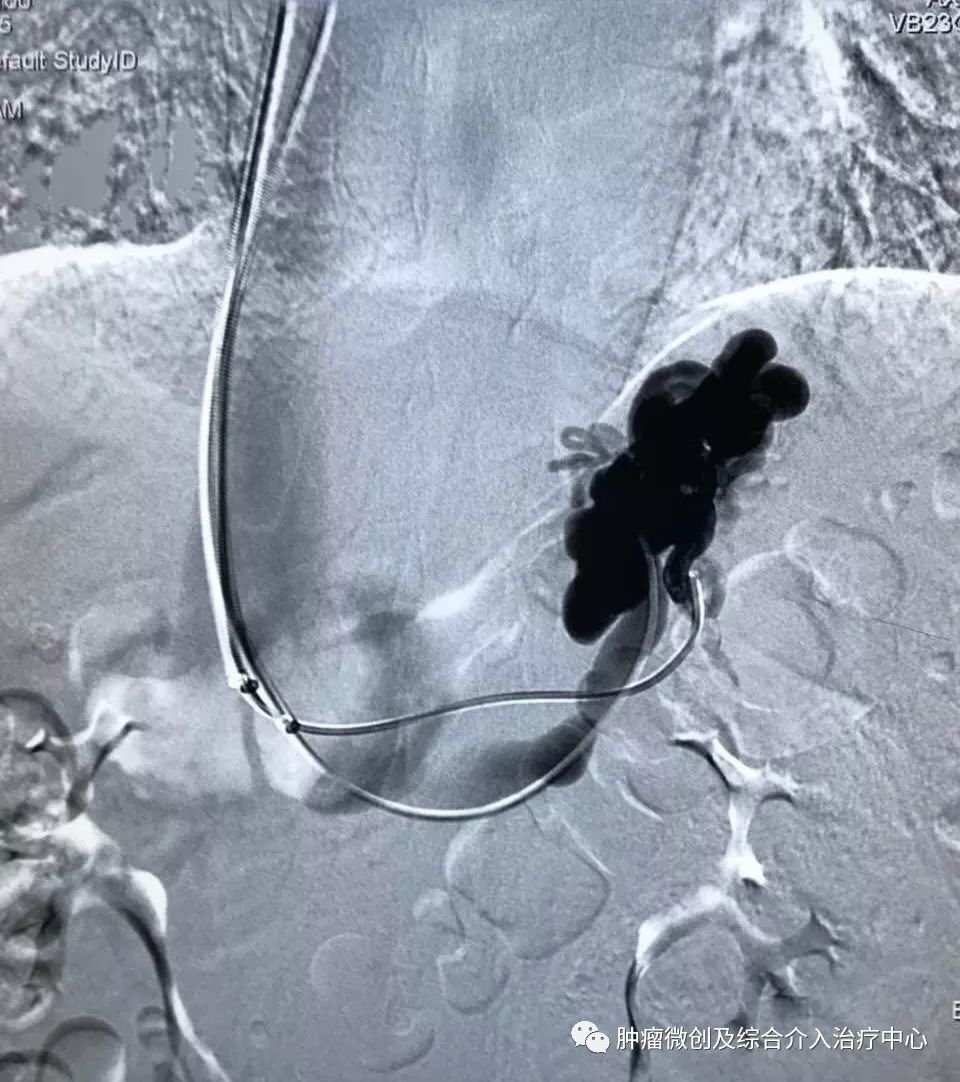

(经皮穿肝-门静脉穿刺成功,门脉高压,门静脉扩张明显)

(食管胃底静脉栓塞术,在血管根部将破裂的上消化道出血血管栓塞完全,即可止血)项目简介:肝硬化门脉高压失代偿期临床表现为反复消化道出血等,患者一般情况欠佳,传统治疗难以改善。食管胃底静脉+胃冠状静脉栓塞术暨经皮肤穿门脉食管胃底+胃冠状静脉栓塞明显降低因消化道大出血导致休克及死亡的风险; 结合内科治疗,其顽固性腹水症状可迅速消退,改善患者生活质量。10肝硬化门脉高压失代偿介入治疗(TIPS术)